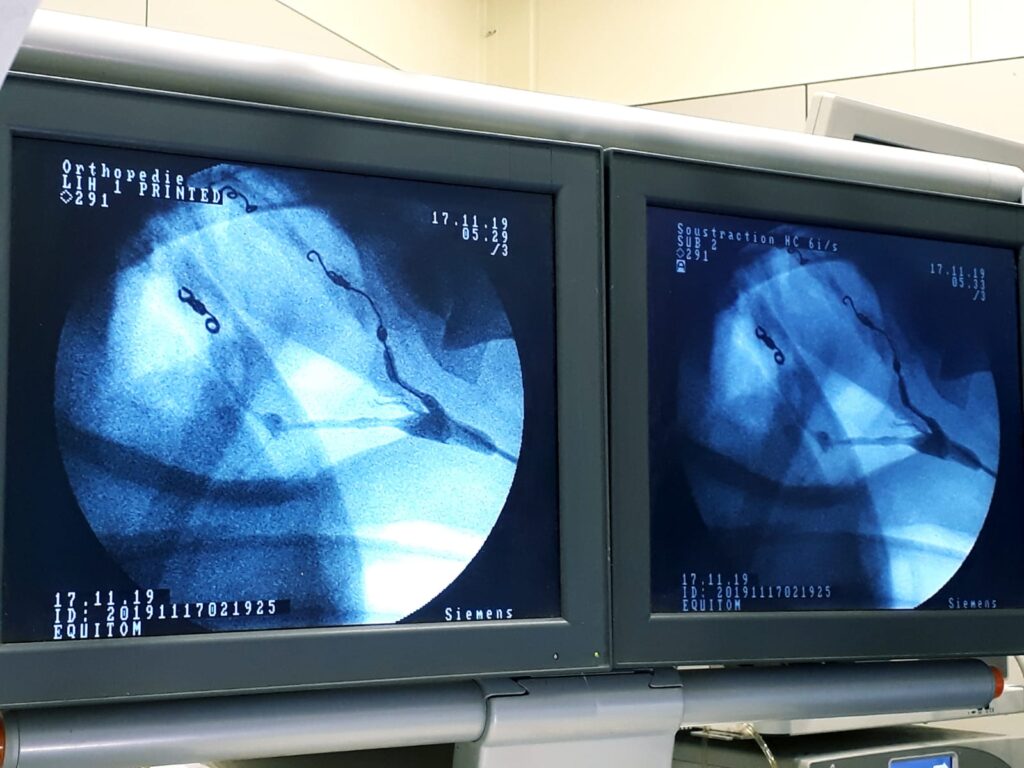

Nejúspěšnější a nejmenšími komplikacemi doprovázená se ukázala technika embolizace (ucpání cévy) pomocí pružiny, kterou využívají veterináři v Equitomu. Původ této metody je v humánní medicíně, konkrétně v radiologii. Zákrok se provádí pomocí katetru zaváděného krkavicí do postižených tepen (obr. 6).

To zahrnuje aplikaci kontrastní látky do tepny a použití speciálního zobrazovacího přístroje (fluoroskopu). S jejich pomocí je možné nalézt cestu k poškozené cévě. Do poškozeného místa se pak katetrem zavede speciální pružina, která napadenou cévu ucpe (obr. 7).

Tyto pružiny se umísťují do nejvyššího a nejnižšího místa vzdušného vaku tak, aby se zabránilo jak běžnému, tak zpětnému toku krve do všech velkých tepen, které procházejí stěnou postiženého vzdušného vaku.